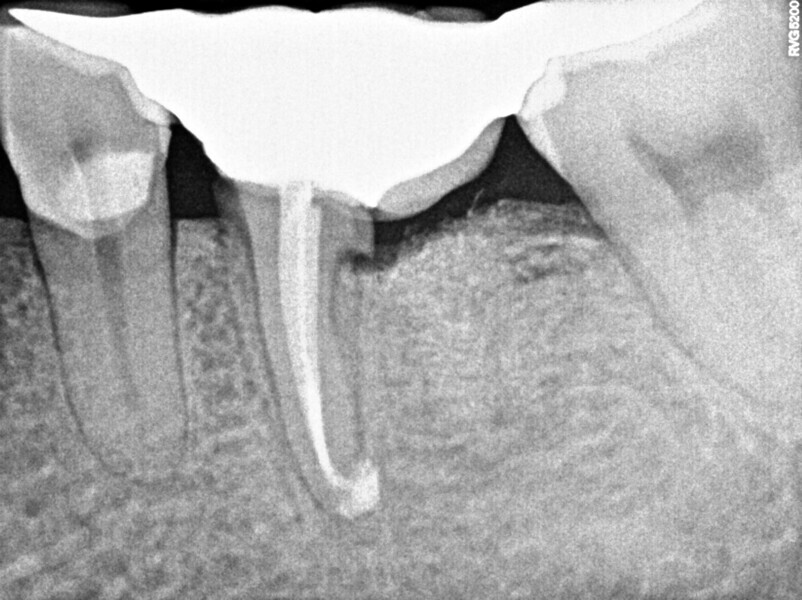

Upon this finding, the hemisection procedure was discussed with the patient, and he gave his full consent to perform it. Initially, the distal canal was gently irrigated with sodium hypochlorite at a 5% concentration and the canal medicated with calcium hydroxide (Fig. 3). At a second appointment 15 days later, the buccal abscess had receded (Fig. 4). The mesial root canal was then treated conventionally, determining the working length with an electronic apex locator (Root ZX II; Morita), performing instrumentation with nickel–titanium files (Pro-Flexi Files, Denco) and obturating with gutta-percha and a bioceramic sealer using the single-cone technique (CeraSeal, Meta Biomed). A resin core was placed with a dual-polymerising composite (CompCore AF, Premier Dental; Figs. 5 & 6).

Thereafter, the hemisection procedure was done under local anaesthesia (4% articaine with 1:100,000 adrenaline; Septodont). Under the microscope, an intra-sulcular incision was performed with a #15C blade, and a partial-thickness flap without vertical incisions was raised to observe the furcal area and resect the distal root and its coronal portion with a fissure diamond bur (Figs. 7–9). Curettage of the granulation tissue was performed and the area rinsed with saline, and a synthetic bone graft (DM Bone, Meta Biomed) was placed in the alveolar socket (Fig. 10). Posteriorly, the flap was repositioned and sutured with #6-0 polypropylene material. The sutures were removed seven days later, and the patient was followed up until three months later. At this point, the tissue had healed, and the definitive restoration procedure was initiated. The tooth remnant was prepared, and a fixed bridge with two cast metal extensions cemented on to previously prepared rests on the occlusal aspect of the neighbouring teeth was placed (Fig. 11).

One year later, the restoration was performing well and the patient was asymptomatic. Radiographs and a CBCT control scan showed complete bone healing. On the periapical radiograph, the tooth showed a healthy periodontal ligament and no signs of failure in the restoration (Fig. 12). The cross-sectional, axial and coronal views of the CBCT scan showed good bone width and height and no pathological findings (Figs. 13–16). The oclusal scans and clinical images showed good adaptation of the new restoration and a healthy gingiva (Figs. 17–20).